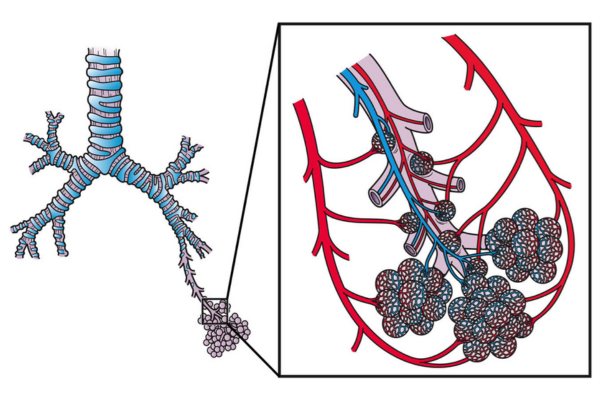

Hemoptysis is coughing up blood due to abnormal or enlarged bronchial arteries. It can be life-threatening if bleeding is severe or recurrent.

Bronchial artery embolization blocks the bleeding vessel using catheters, controls hemorrhage quickly, avoids surgery, and stabilizes the patient safely.

Pulmonary arteriovenous fistulas are abnormal connections between pulmonary arteries and veins, leading to poor oxygenation and risk of stroke.

Embolisation closes these abnormal channels using coils or plugs, improves oxygen levels, prevents complications, and restores normal lung circulation safely.